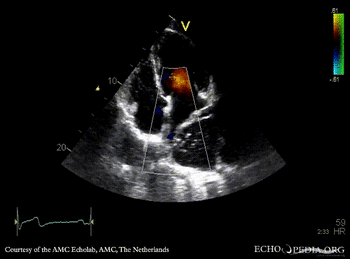

| A4CH | A4CH color doppler |